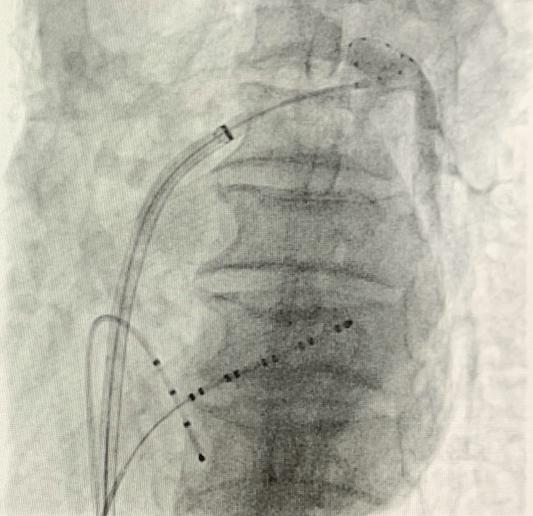

(手术过程)